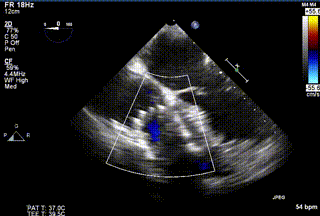

三例患者入院后,葛均波院士團隊周達新教授、潘文志教授、張源博士、陳莎莎博士及心超室的潘翠珍教授、李偉教授對患者的情況進行詳細評估和討論,最終決定為三例患者選擇LuX-Valve Plus40mm、50mm和50mm型號的瓣膜進行手術治療。手術后即刻拔除氣管插管,術后患者三尖瓣反流癥狀得到顯著改善,復查心超結果顯示人工三尖瓣瓣膜支架固定穩定,瓣葉關閉形態未見異常,未見明顯反流。